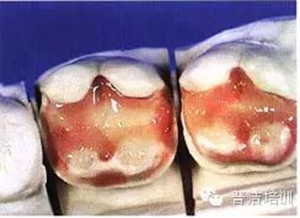

五、采用分層充填技術(shù)充填樹(shù)脂,恢復(fù)牙體原有的色澤和形態(tài)

六。用透明樹(shù)脂修復(fù)舌側(cè)壁

七、光照后,修復(fù)體完成

八、在可卸帶型上的樹(shù)脂嵌體,拋光